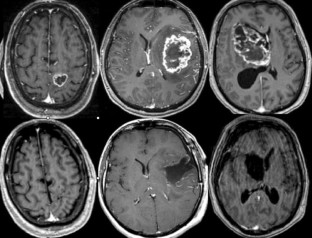

Fig. 1

Fig. 2

Fig. 3

Fig. 4

Fig. 5

We analyzed the efficacy and applicability of surgery guided by 5-aminolevulinic acid (ALA) fluorescence in consecutive patients with glioblastoma multiforme (GBM). Thirty-six patients with GBM were operated on using ALA fluorescence. Resections were performed using the fluorescent light to assess the right plane of dissection. In each case, biopsies with different fluorescent quality were taken from the tumor center, from the edges, and from the surrounding tissue. These samples were analyzed separately with hematoxylin–eosin examination and immunostaining against Ki67. Tumor volume was quantified with pre- and postoperative volumetric magnetic resonance imaging. Strong fluorescence identified solid tumor with 100% positive predictive value. Invaded tissue beyond the solid tumor mass was identified by vague fluorescence with 97% positive predictive value and 66% negative predictive value, measured against hematoxylin–eosin examination. All the contrast-enhancing volume was resected in 83.3% of the patients, all patients had resection over 98% of the volume and mean volume resected was 99.8%. One month after surgery there was no mortality, and new or increased neurological morbidity was 8.2%. The fluorescence induced by 5-aminolevulinic can help to achieve near total resection of enhancing tumor volume in most surgical cases of GBM. It is possible during surgery to obtain separate samples of the infiltrating cells from the tumor border.